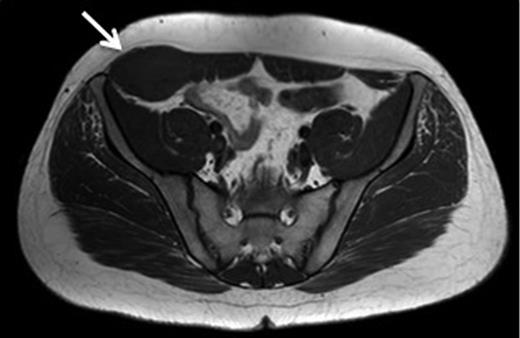

A 31-year-old man presented to his General Practitioner in May 2012 with a 6-week history of a painful mass in the right iliac fossa. There was no regional lymphadenopathy and hip examination was unremarkable. He was a smoker with a BMI of 33 and had undergone a right-sided inguinal hernia synthetic mesh repair in 2010. MRI with contrast confirmed a 6.9 × 6.7 × 4.6 cm mass invading the abdominal wall musculature (Fig. 4). Radiological features were suggestive of sarcoma or aggressive fibromatosis. Histology from an ultrasound-guided biopsy revealed aggressive fibromatosis. The patient opted for a surgical excision of the mass with abdominal wall reconstruction. The tumour was excised with the internal oblique, leaving the peritoneum and external ring cord structures intact. A 13 × 15 cm sheet of porcine intestinal biological mesh was used to repair the abdominal wall defect (Fig. 5). Inferiorly, the mesh was doubled over in the pre-peritoneal space to reconstruct the inguinal ligament, and sutured to the external oblique. The histology confirmed a final diagnosis of aggressive fibromatosis excised with 1 mm margins. At 24 months, there was good wound healing and no hernia, seroma or evidence of recurrence on follow-up MRI.

T1 MRI showing a soft tissue tumour of the anterior abdominal wall involving external oblique and internal oblique and not involving the peritoneum.